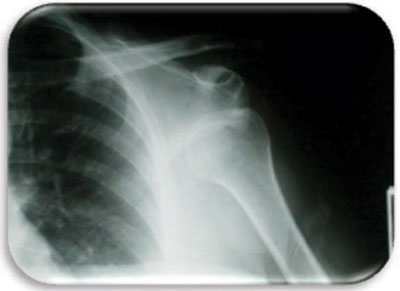

قال الدكتور عمران حنيف استشاري جراحة العظام والإصابات الرياضية في المجمع الطبي في العليا والحاصل على الزمالة الإيرلندية إن حالات خلع الكتف المتكرر لا يصلح معها العلاج التحفظي فيلجأ الكثير من الجراحين إلى العلاج الجراحي بهدف منع خروج رأس عظمة الذراع وتحديد مجال الدوران الخارجي للمفصل، موضحاً أن العلاج الجراحي ينقسم إلى نوعين أو أسلوبين، الأول هو المنظار الجراحي للكتف، حيث يتم إصلاح قطع حافظة وأربطة الكتف بواسطة المنظار وبمساعدة خطاطيف معدنية صغيرة لإعادة تثبيت حافظة الكتف، وتعد هذه الطريقة مثالية في معظم الحالات، حيث إنها تتميز بنسبة نجاح عالية جداً مع سرعة عودة المريض إلى عمله، وذلك دون وجود ندبات جراحية ملحوظة.

أضاف الدكتور عمران حنيف أن الأسلوب الثاني هو الجراحة المفتوحة الذي يعتمد على إعادة بناء أربطة وعضلات الكتف، وتستعمل هذه الطريقة في الحالات المهملة لفترات طويلة، حيث تكون العضلات الأمامية للكتف في حالة ضعف شديدة وتحتاج إلى إعادة البناء، كما تتميز هذه الطريقة بنسبة نجاح فائقة مع درجة عالية جداً من ثبات المفصل وتتم من خلال جروح صغيرة للغاية تكون من تحت الإبط، حيث لا يظهر ندبات خارجية بشكل ملحوظ، وذلك مراعاة للشكل الجمالي، مشيراً إلى أنه في كلا الأسلوبين يعد العلاج الطبيعي والتأهيلي لمفصل الكتف بعد العملية عاملاً مهما في نجاحها.

الخلع الحاد أحد الأسباب وقال أن الخلع المتكرر لمفصل الكتف هو أكثر مضاعفات الخلع الحاد شيوعاً نتيجة عدم التزام المريض بخطوات علاج الخلع الحاد وإهمال إجراء الرنين المغناطيسي لتقييم الضرر الناشئ في أربطة مفصل الكتف، حيث لا تتوافر فرصة للأربطة ولا للكبسولة ولا للعضلات للشفاء والعودة إلى الحالة الطبيعية فتبقى هذه الأنسجة في حالة التئام معيبة ومرتخية فيسهل حدوث فك مرة أخرى للكتف لأتفه الأسباب، ومع تكرار حدوث الفك للكتف تزداد الأنسجة ارتخاء، ويفقد المفصل حساسية الوجع بسبب إصابة الأعصاب فيحدث الفك لمفصل الكتف حتى في مجال الحركة الطبيعية للمفصل.

أضاف استشاري طب وجراحة العظام أن الشباب والرياضيين هم أكثر المتأثرين بهذا المرض نتيجة للنشاط الزائد وممارسة التمارين الرياضية بجوار عوامل أخرى تؤدي لحدوث الخلع المتكرر، منها عدم الحفاظ على تثبيت مفصل الكتف لمدة أربعة أسابيع، وعدم تقوية العضلات المحيطة بالمفصل بالعلاج الطبيعي، وطريقة حدوث الإصابة ودرجة التمزقات والكسور المصاحبة، إضافة إلى عامل العمر، فكلما كان عمر المريض أقل من الـ20 زادت احتمالات الفك المتكرر، مؤكداً في نهاية حديثه أهمية إجراء صورة الرنين المغناطيسي التي تعد من العوامل المساعدة في تحديد مدى إصابة أربطة وحافظة مفصل الكتف وتحديد طريقة العلاج.